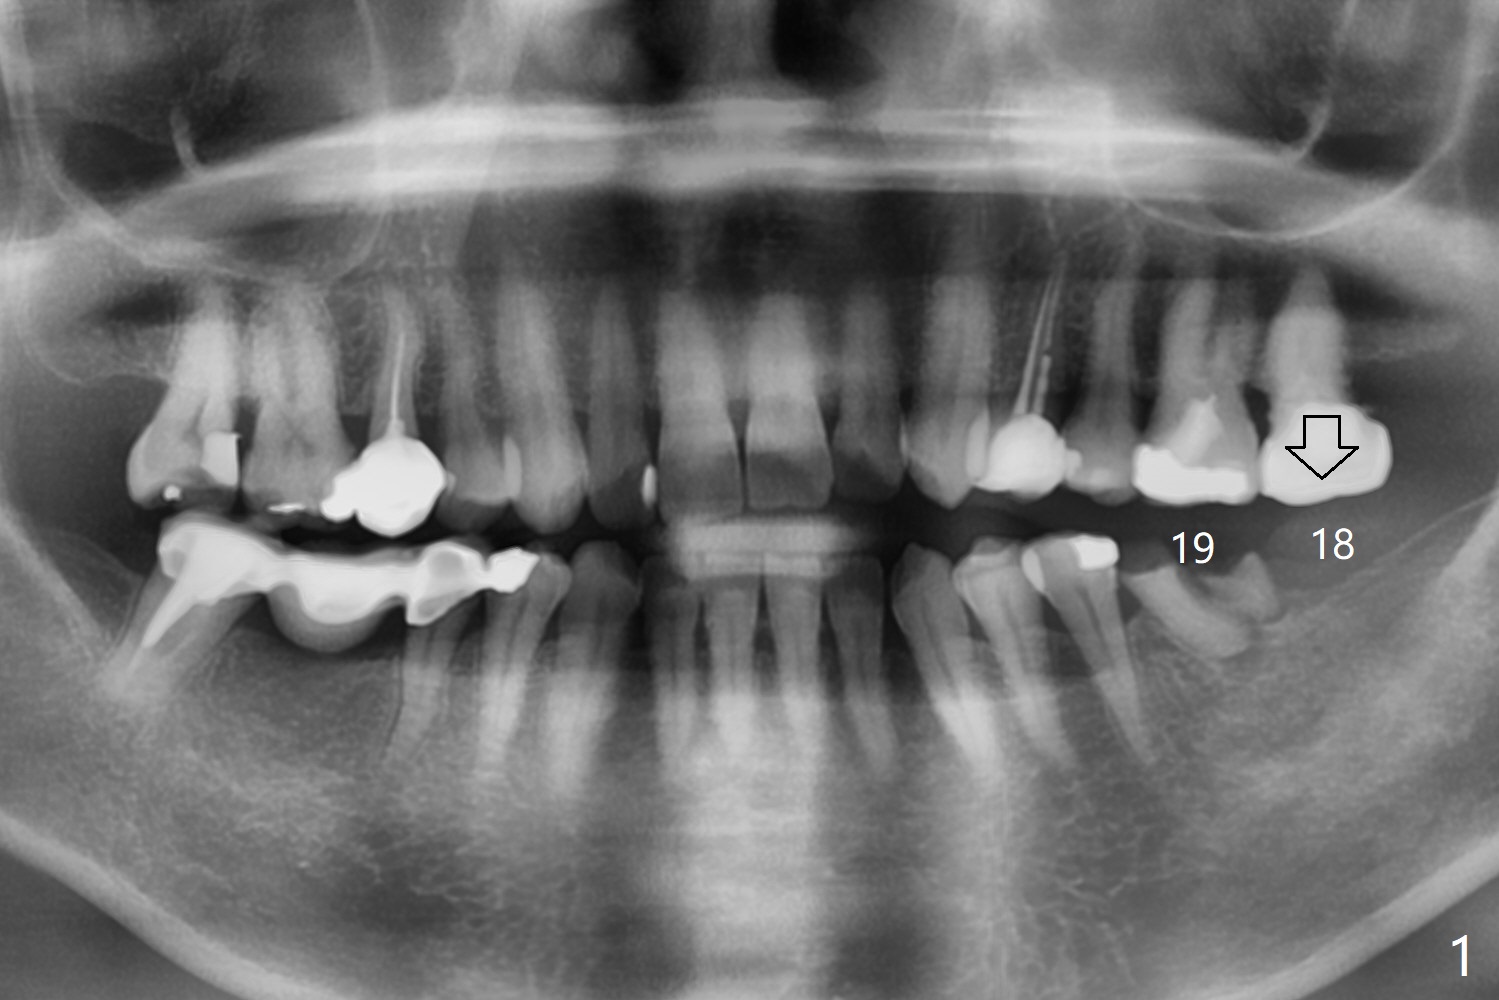

A 57-year-old woman agrees to have implants at #18 and 19 (Fig.1). Since the tooth #15 is supraerupted and there is limited vertical space at #18 (Fig.3), Magicore and FC will be placed at #18 and 19, respectively (Fig.3,2).